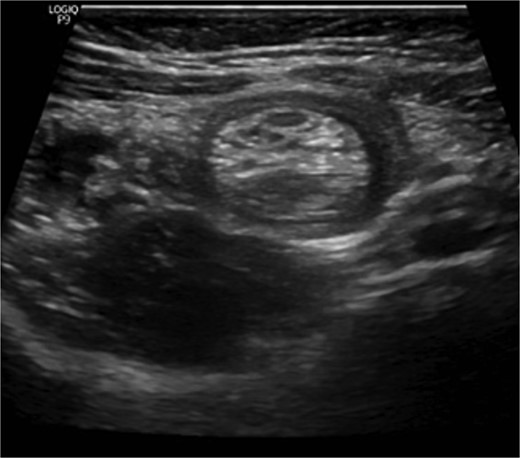

The blood tests showed raised inflammatory markers. An abdominal ultrasound confirmed the presence of intussusception (Fig. 2). A decision was made for a laparoscopic reduction of the intussusception and inspecting for a leading point. A MD was demonstrated and resected accordingly (Fig. 3). The location of intussusception was at the ileo-cecal area. The affected bowel was viable. The position of the MD was in the terminal ileum and it was the lead point for the intussusception. No lymph node involvement. Also, a tumor located at the base of the MD ~4 mm from the resection margin, was found and resected.

Meckel’s diverticulum as a lead point for recurrent intussusception.